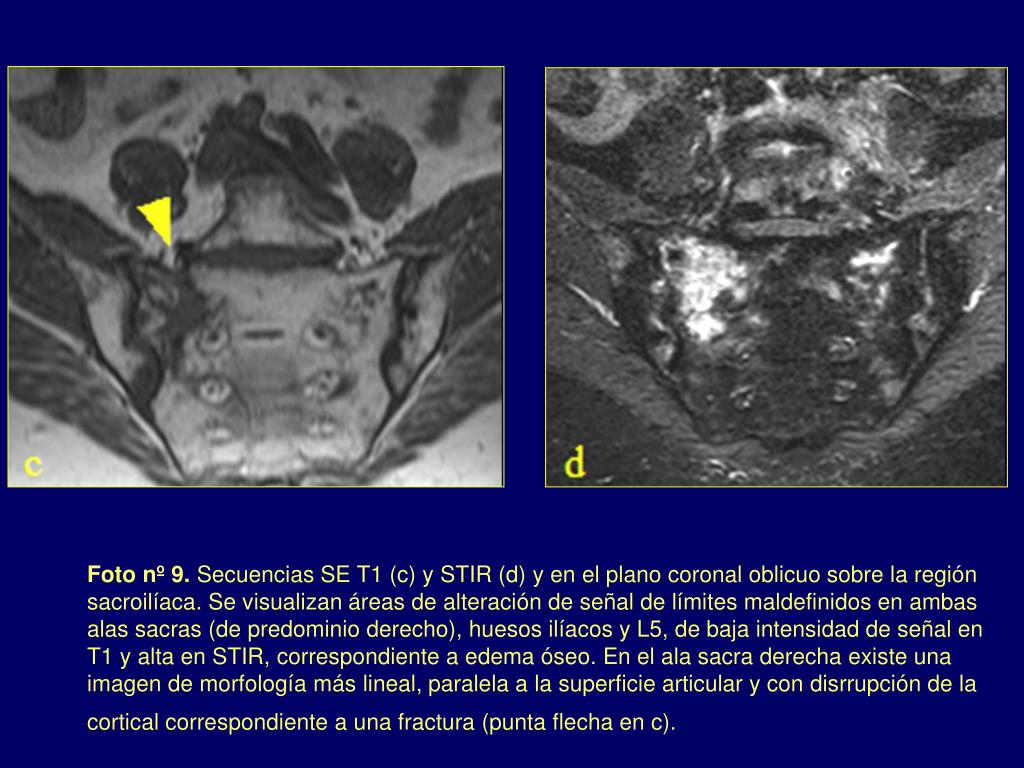

10. Foto nº 9. Secuencias SE T1 (c) y STIR (d) y en el plano coronal oblicuo sobre la región sacroilíaca. Se visualizan áreas de alteración de señal de límites maldefinidos en ambas alas sacras (de predominio derecho), huesos ilíacos y L5, de baja intensidad de señal en T1 y alta en STIR, correspondiente a edema óseo. En el ala sacra derecha existe una imagen de morfología más lineal, paralela a la superficie articular y con disrrupción de la cortical correspondiente a una fractura (punta flecha en c).